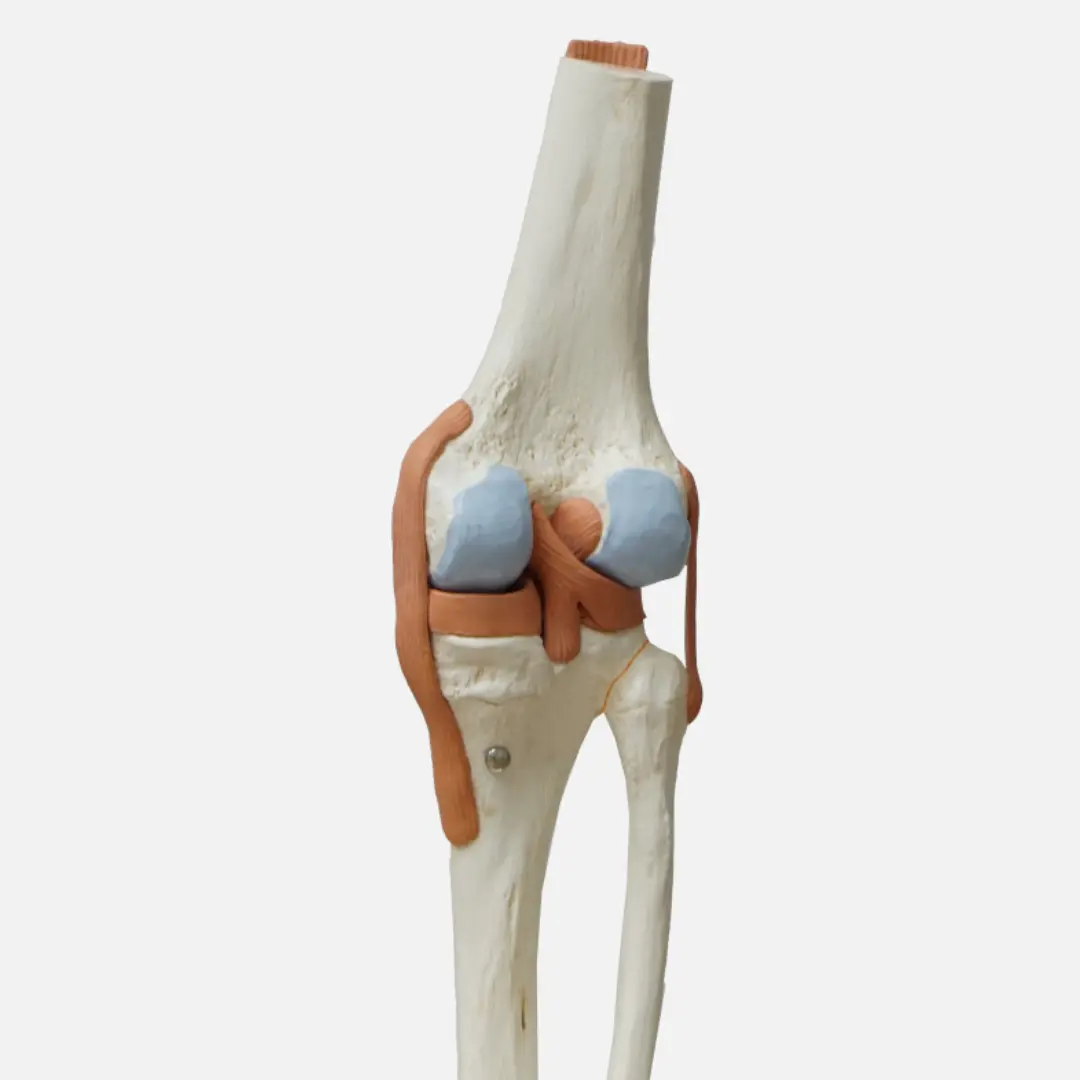

혹시 계단을 오르내릴 때 무릎이 시큰거리거나, 아침에 일어나면 손가락 마디가 뻣뻣하신가요? 그렇다면 관절 건강에 적신호가 켜졌을 가능성이 높아요. 지금부터 관절 건강 도움되는 관절영양제에 대해 자세히 알아보고 어떤 관절영양제가 나에게 맞는지 관절영양제 추천부터 선택 꿀팁까지 알아볼게요!

관절 건강은 나이가 들수록 중요해져요. 특히 다음과 같은 분들은 관절영양제 섭취를 고려해 보는 것이 좋아요.

관절 건강에 도움을 주는 주요 성분들을 꼼꼼히 따져보고 나에게 필요한 성분이 들어있는지 확인해 보세요.